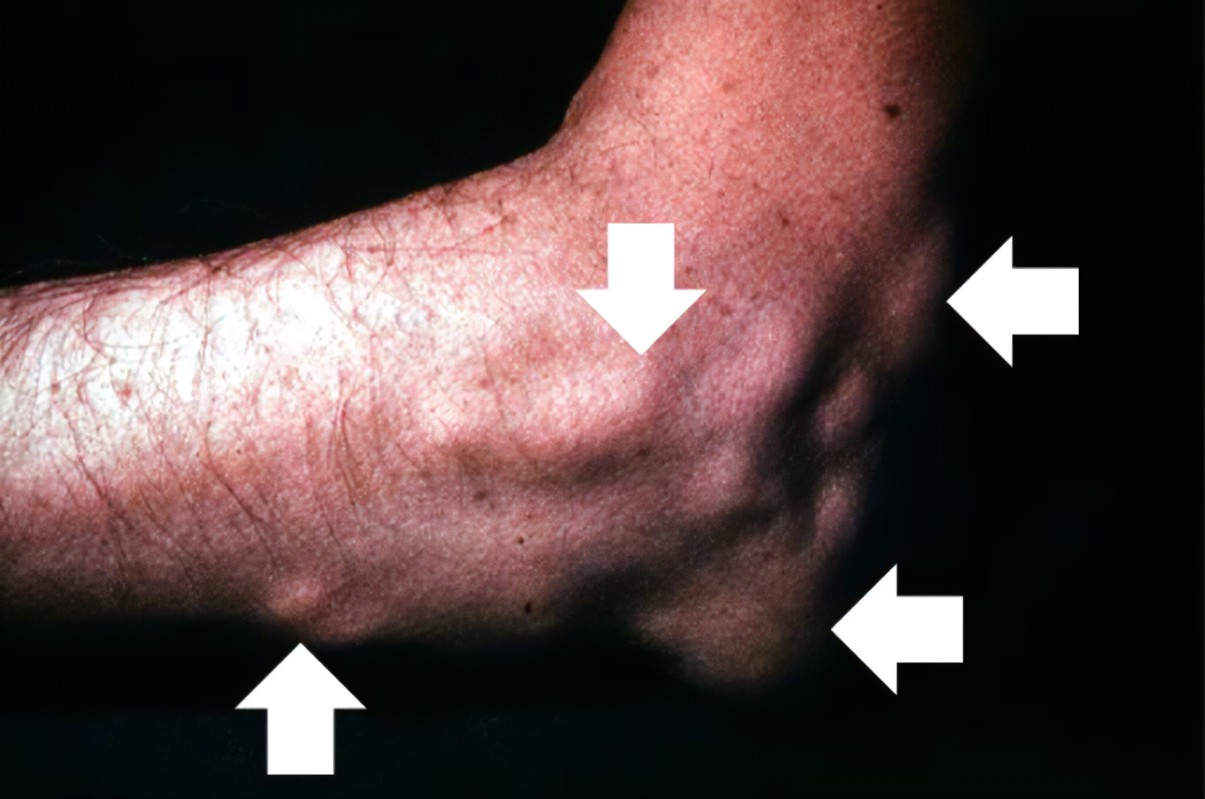

在痛风患者当中 , 最常见的表现就是发现关节附近有石头一样的东西 。 这种情况非常普遍 , 我们也称这种石头为:

痛风石 。

由于身体中的代谢失衡 , 血液中的尿酸钠越来越多 , 这导致在关节部位出现了结晶沉淀 。

有学者认为 , 这是身体各部位温度不同导致的 。 因为肢体远端的温度会稍低一些 , 我们正常的身体温度差不多是37℃左右 , 而膝关节关节腔内的温度差不多是32℃ 。

这导致在血液中溶解的尿酸 , 反倒是在关节内变成了晶体 。

痛风石就是这么来的 。